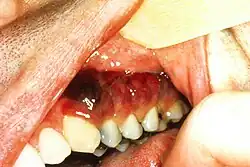

Zmiany w obrębie głowy i szyi przed pandemią AIDS były rzadkie[38]. Obecnie zmiany w obrębie skóry i błon śluzowych okolicy głowy i szyi dotyczą przede wszystkim chorych na AIDS, u których jest to jedna z najczęstszych lokalizacji zmian w przebiegu mięsaka Kaposiego[5][39]. U blisko 70% chorych na mięsaka Kaposiego związanego z AIDS stwierdza się wykwity w zakresie skóry twarzy, skalpu i szyi, a u blisko 60% w obrębie jamy ustnej, jamy nosowej, gardła i krtani[5]. U 13% stwierdza się powiększone węzły chłonne tej okolicy[5]. Rzadko stwierdza się zmiany w spojówkach, gruczołach łzowych, śliniankach, migdałkach i mięśniu żwaczu[5]. Zmiany zwykle są bezobjawowe, ale mogą powodować ból, krwawienie, ulegać owrzodzeniu, wtórnym zakażeniom oraz wywoływać objawy poprzez ucisk innych struktur[5][37].